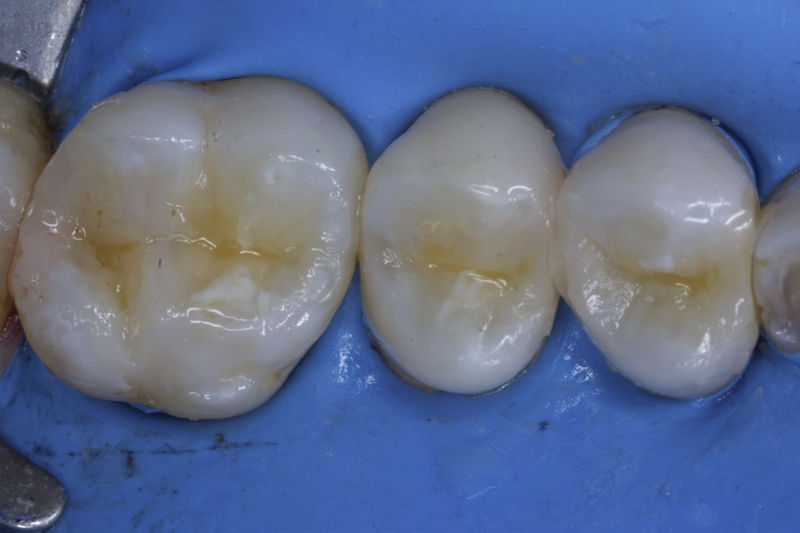

Restauraciones fabricadas en el laboratorio con materiales estéticos, los cuales cubren de manera parcial dientes posteriores. Se utilizan primariamente para restaurar dientes con caries, fracturas y/o defectos amplios. Para poder enviar el caso al laboratorio se toman impresiones utilizando materiales de impresión o técnicas modernas digitales.

Restauraciones fabricadas en el laboratorio con materiales estéticos, los cuales cubren de manera total dientes anteriores y posteriores. Se utilizan primariamente para restaurar dientes con caries, fracturas y/o defectos amplios, así como soportes de puentes. Para poder enviar el caso al laboratorio se toman impresiones utilizando materiales de impresión o técnicas modernas digitales.